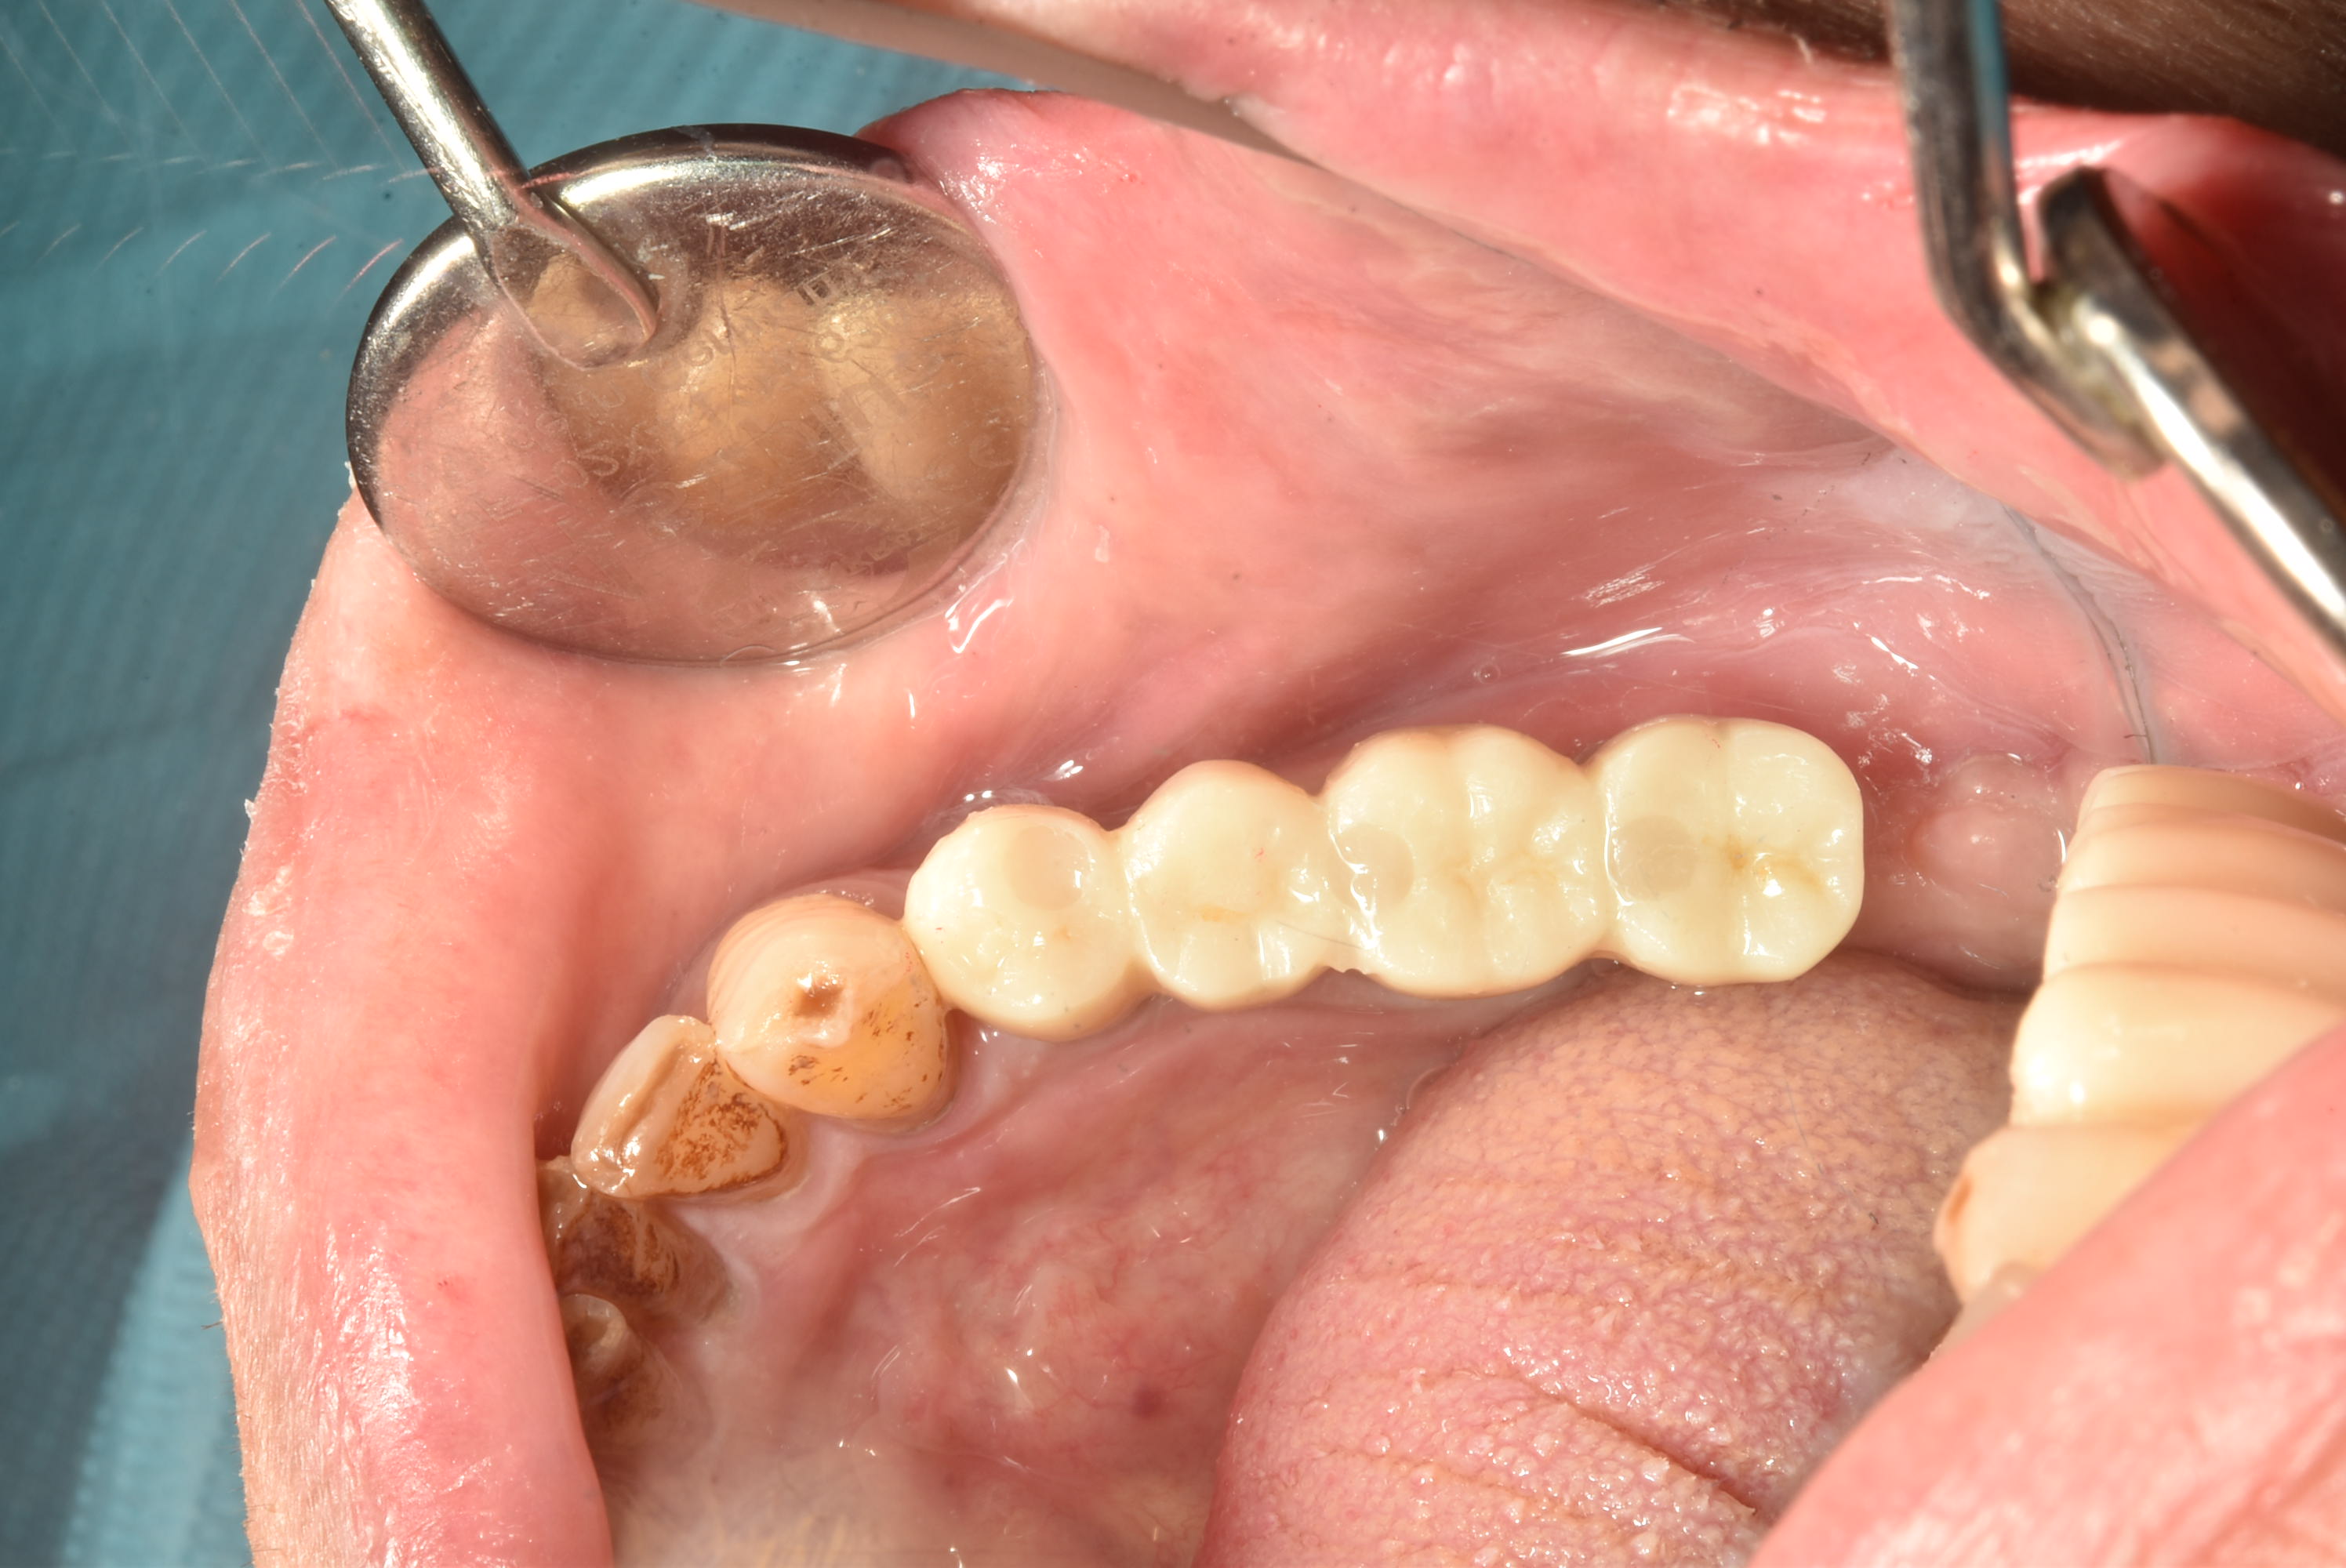

案例一

立即拔除,當天完成植牙手術,並鎖上癒合螺帽

2-3月癒合,取下癒合螺帽,透過數位口掃至技公所製作假牙

7-10天完成假牙,試戴、調整咬合高度並鎖上

封填,完成